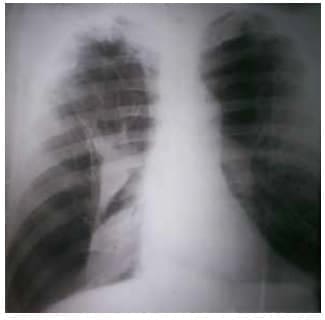

En la radiografía postero-anterior inicial de tórax en bipedestación se encontró colapso del pulmón derecho con múltiples bullas enfisematosas en ambos campos pulmonares (figura 1).

Figura 1. Radiografía de tórax, postero-anterior y en bipedestación,

en la que se observa el colapso del pulmón derecho con

múltiples bullas enfisematosas en ambos campos pulmonares.

El lóbulo superior derecho presentaba signos de atrapamiento de aire por la existencia de enfisema pulmonar, con aumento de su radiotransparencia. Las costillas se encontraban ‘horizontalizadas’ y había ensanchamiento de los espacios intercostales, y descenso y aplanamiento del diafragma.